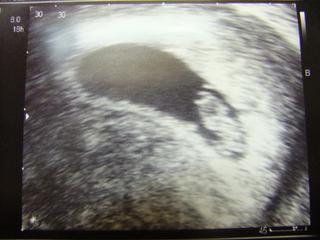

Tak mame za sebou dalsie sono,potvrdena ziva gravidita,srdiecko bije.Idem na śkrinin´g koli genetike a potom dostanem aj knizku.Od pondelka nastupujem do prace,aj sa tesim na baby,lebo mi doma bolo za nimi smutno.Tak dufam,ze to bude v pohode.Pekny den vam prajem.

AHoj hlasim sa po dlhej dobe a dnesnej navsteveu gyn. Drobceka som konecne videla krasne mu bilo srdiecko ale podla rozmerov ovulka nebola posunuta o tyzden ale az o 10 dni takze mi termin vychadza skor na november.. Tehu knizku este nemam, len mi urobili foto a dokrvili ma. Dnes to bolo 7tt+2.